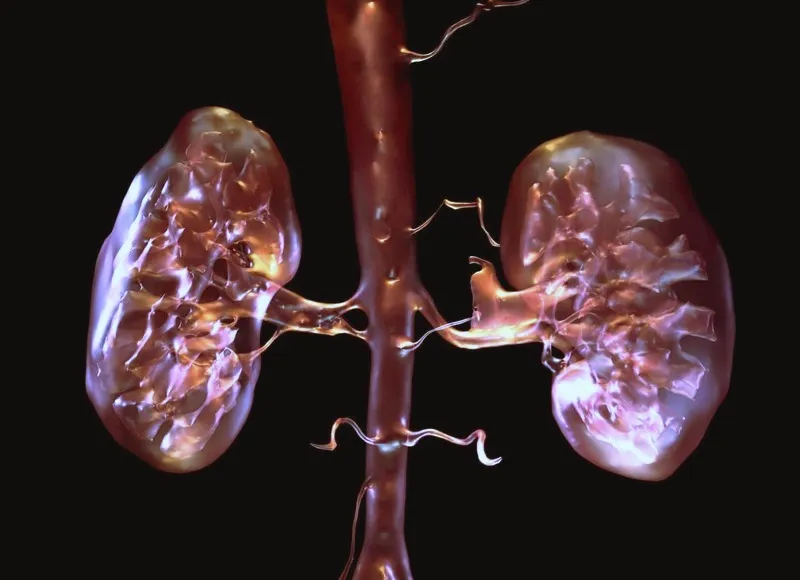

Наркотические соединения выделяются с мочой, некоторые удаляются через кишечник. Психоактивные соединения — универсальные токсины. Как и все вещества этого типа, они быстро разрушают любые ткани организма. Падение фильтрующей функции отражается развитием нескольких патологий:

- Пиелонефрита — снижение местного иммунитета, активация условно-патогенной флоры сказывается воспалительным процессом. Заболевание прогрессирует медленно, но уверенно.

- Гломерулонефрита — воспаление аутоиммунного характера развивается после отказа от наркотиков, как реакция на восстановления работы защитных сил. Может привести к острой почечной недостаточности.

- Острая почечная недостаточность — результат действия избытка веществ при больших количествах потребляемого наркотика. Состояние смертельно опасное, может привести к гибели в считаные сутки.

- Хроническая почечная недостаточность развивается постепенно, проявляется снижением качества фильтрующей функции почек вплоть до полной остановки работы парного орга́на. Разрушение почек сопровождается ростом артериального давления, снижением количества суточной мочи, отёками.

- Нефропатия — собирательное название иных нарушений фильтрующей функции, которые пока не перешли в хроническую почечную недостаточность.

Лечением почечных патологий занимаются нефрологи или специалисты более широкого профиля — урологи. Терапия консервативная, реже — оперативная, вплоть до трансплантации почки.